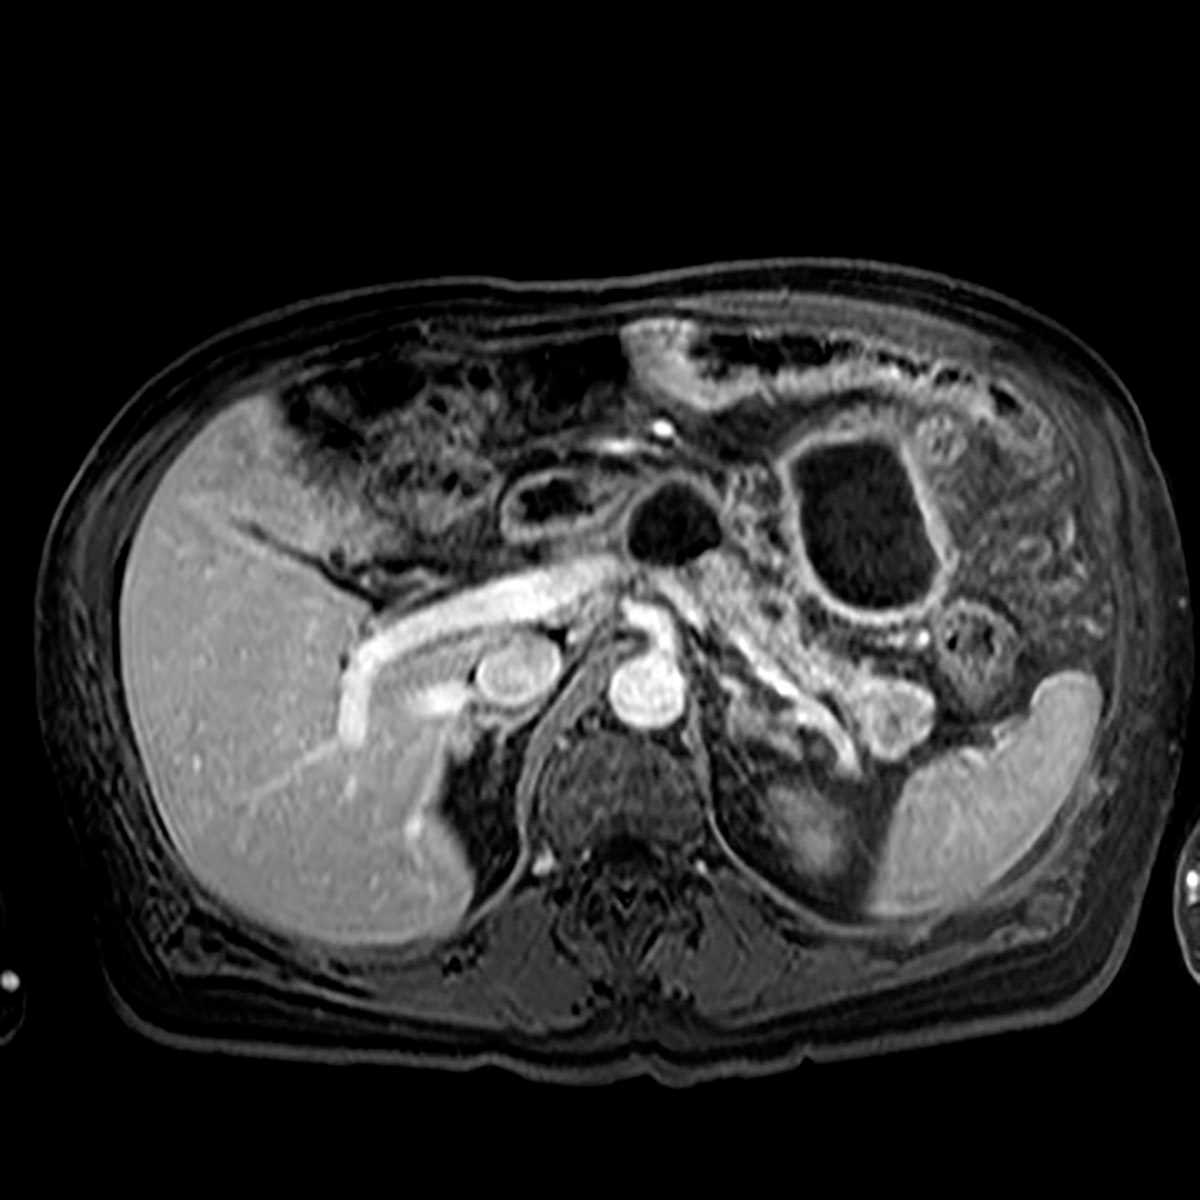

Chronic pancreatitis

Multiple MRI images demonstrate diffuse T1 hypointensity of the pancreas with a dilated pancreatic duct and at least 2 discrete cystic lesions in communication with the pancreatic duct, representing chronic pancreatitis with pseudocysts